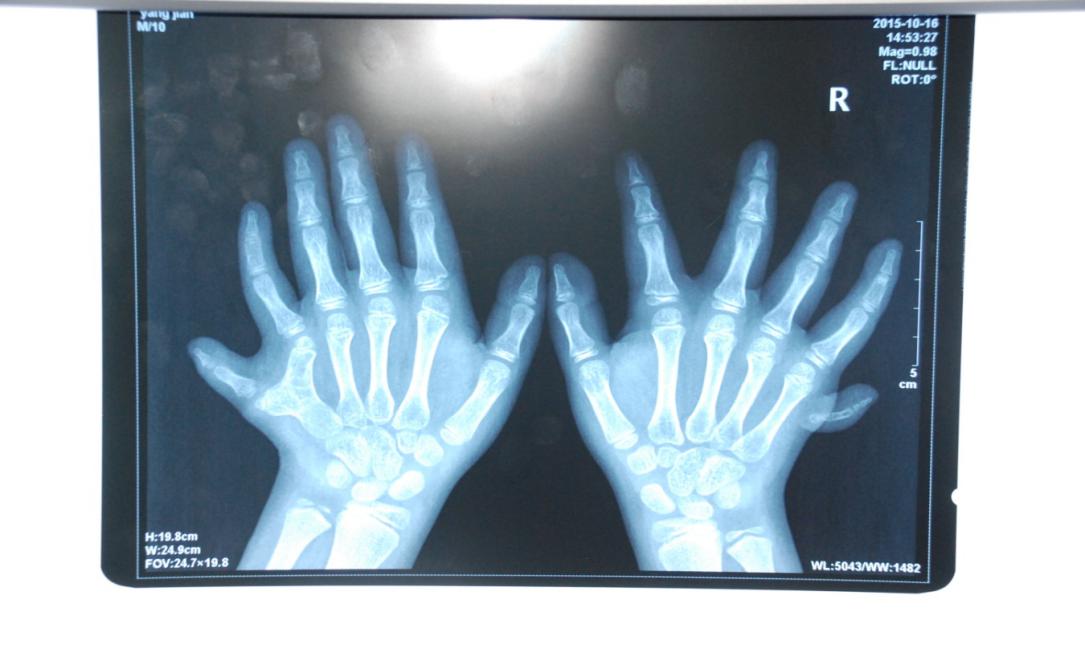

廈門眼科中心小兒眼科修陽暉博士在日常的診療過程中就接診了不少這樣的的特殊家庭,讓其尤為印象深刻的就是一年前接診的BBS綜合征患者。當時來院就診的是一對親兄弟,之前已在多家醫(yī)院做過檢查,因其均有較大散光和斜視,肉眼下眼底檢查未見異常,故外院均診斷為弱視,這也符合眼科門診常規(guī)的診斷邏輯與思維。但由于兄弟倆均有智力發(fā)育遲緩、特殊面容及四肢均有六指和六趾的特異體征引起了修陽暉博士的警覺:會不會是一種特殊遺傳性疾病或綜合征?后續(xù)的檢查結果進一步證實了修陽暉博士的懷疑---患兒均有夜盲,ERG、VEP及OCT檢查顯示雙眼的視網(wǎng)膜神經(jīng)上皮層結構及功能均明顯異常。由于之前未遇到此種病例,修陽暉博士在診斷一欄寫下視網(wǎng)膜色素變性并打上了個問號,同時留下了病人的聯(lián)系方式。

BBS綜合征(Bardet-Biedl綜合征)是一種主要累及纖毛結構與功能的罕見常染色體隱性遺傳性疾病。纖毛分布于哺乳動物體內(nèi)的大多數(shù)細胞,它是一種廣泛存在于各種細胞表面的細胞器,體型微小但結構復雜、作用強大,能感知細胞外機械和化學信號變化并協(xié)助其轉導到細胞內(nèi)部從而引起細胞應答。高等動物的視覺、觸覺、嗅覺、聽覺的傳遞都依賴于體內(nèi)外正常的纖毛結構和功能。因此BBS綜合征常累及全身多個系統(tǒng)和器官,在臨床上主要表現(xiàn)為:視網(wǎng)膜色素變性、智力發(fā)育異常、向心性肥胖、多指(趾)、性腺發(fā)育異常、腎臟異常。除此之外還有許多諸如:語言發(fā)育障礙、聽力異常、嗅覺異常、斜視、白內(nèi)障、散光、牙齒發(fā)育異常、短指(趾)、并指(趾)、肝纖維化、糖尿病、高血壓等表現(xiàn)。